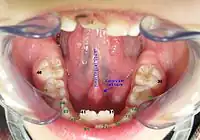

Chez l’homme, la caroncule lacrymale correspond à l’excroissance charnue située à l’angle interne de l’œil. Quant à la caroncule salivaire, elle se trouve au pied du frein lingual : elle supporte les orifices externes des glandes sublinguales et submandibulaires.